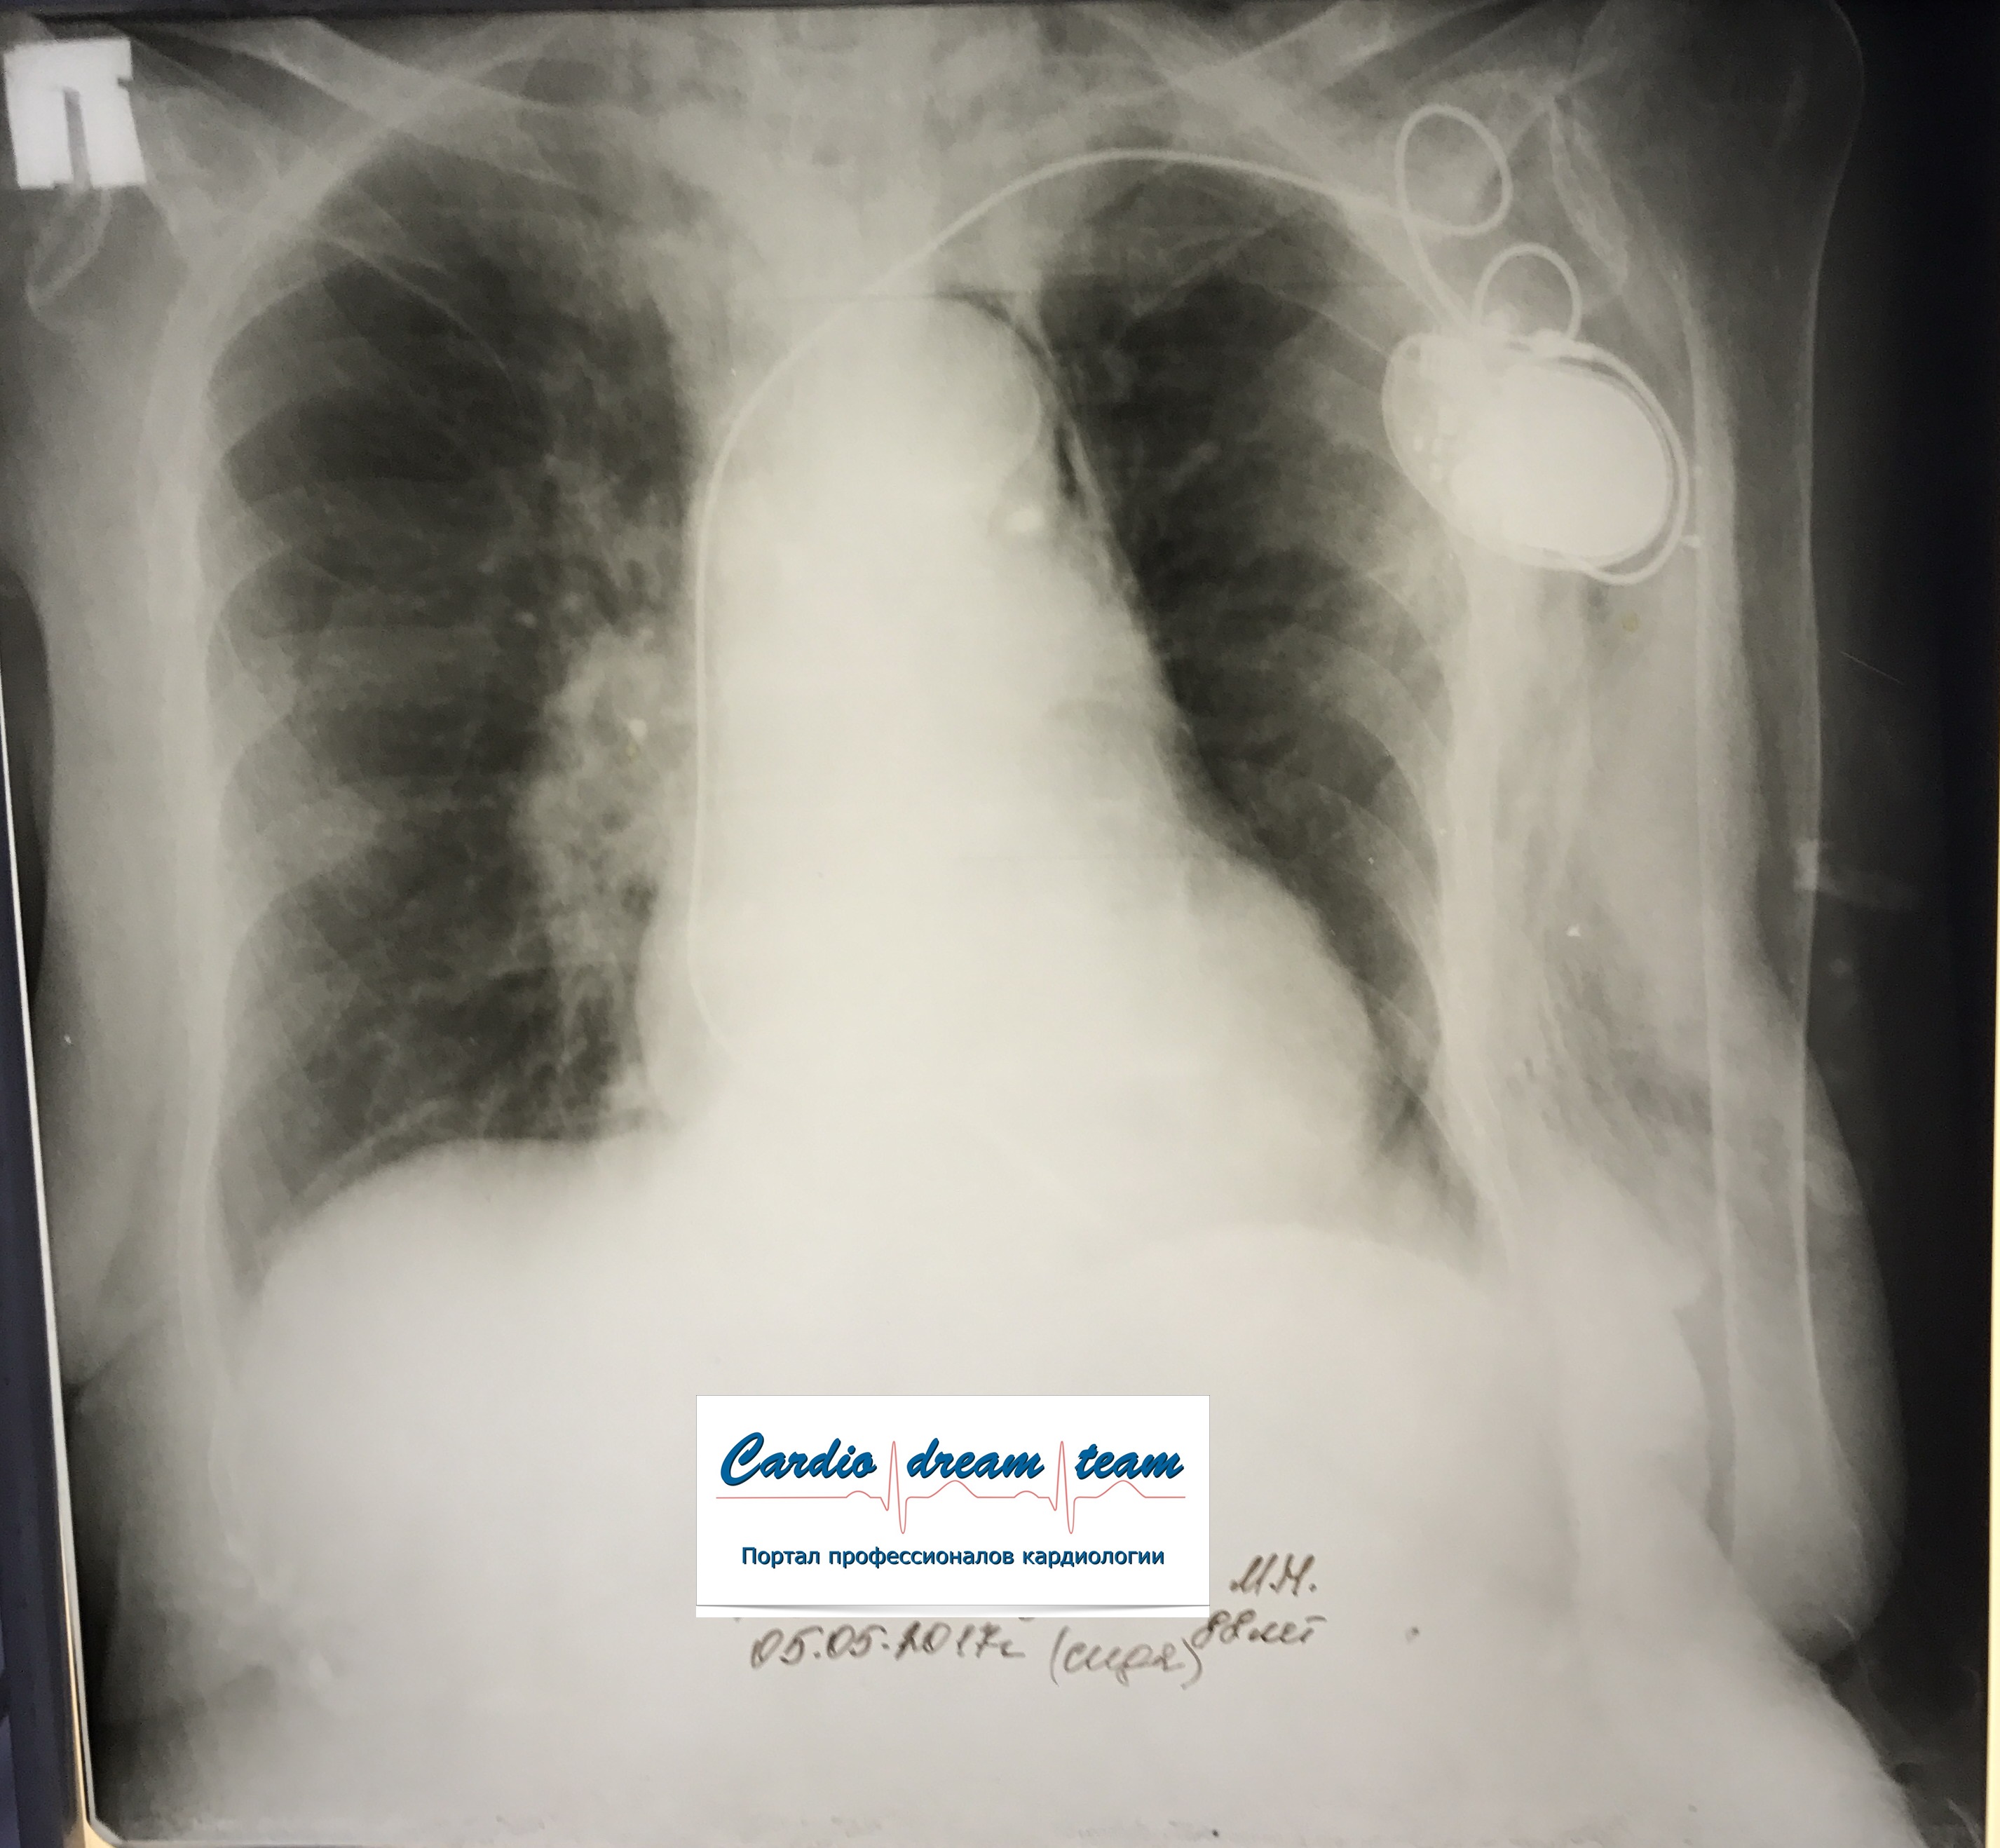

ИССЛЕДОВАНИЕ ОРГАНОВ ГРУДНОЙ КЛЕТКИ Дата 01-ОКТ-15 время 11.30 ОПИСАНИЕ: Проведена рентгенография органов грудной клетки в прямой проекции, положение сидя, условия ПИТ, Р-контроль Легочные поля: Справа легкое расправлено не полностью, апикально до 3го ребра прослеживается свободный газ в плевральной полости. Тень дренажа справа. Тень подключичного катетера в проекции ВПВ. Легочный рисунок: сгущен справа в прикорневой зоне, диффузно деформирован Корни: малоструктурны, обогащены Синусы: нечеткие Сердце: широко лежит на диафрагме (позиционно) ЗАКЛЮЧЕНИЕ: Течение правостороннего пневмоторакса, положительная Р-динамика. Состояние дренирования правой плевральной полости. Р-признаки полнокровия сосудов МКК. Пневмосклероз. Р-контроль .────────────────────────────────────────────────────────────────────── ИССЛЕДОВАНИЕ ОРГАНОВ ГРУДНОЙ КЛЕТКИ Дата 02-ОКТ-15 время 1015 ОПИСАНИЕ:

Проведена рентгенография органов грудной клетки в прямой проекции, положение полусидя, условия ПИТ, Р-контроль Легочные поля: Отрицательная динамика: правое легкое поджато к корню. Тень средостения резко смещена влево. Выраженная подкожная эмфизема мягких тканей грудной клетки справа. Тень подключичного катетера в проекции ВПВ. Легочный рисунок: диффузно деформирован за счет пневмосклероза, сгущен справа Корни: тень средостения смещена влево Синусы: нечеткие Сердце: широко лежит на диафрагме (позиционно) ЗАКЛЮЧЕНИЕ: Правосторонний пневмоторакс, отрицательная Р-динамика. Эмфизема мягких тканей грудной клетки. Пневмосклероз. Р-контроль.